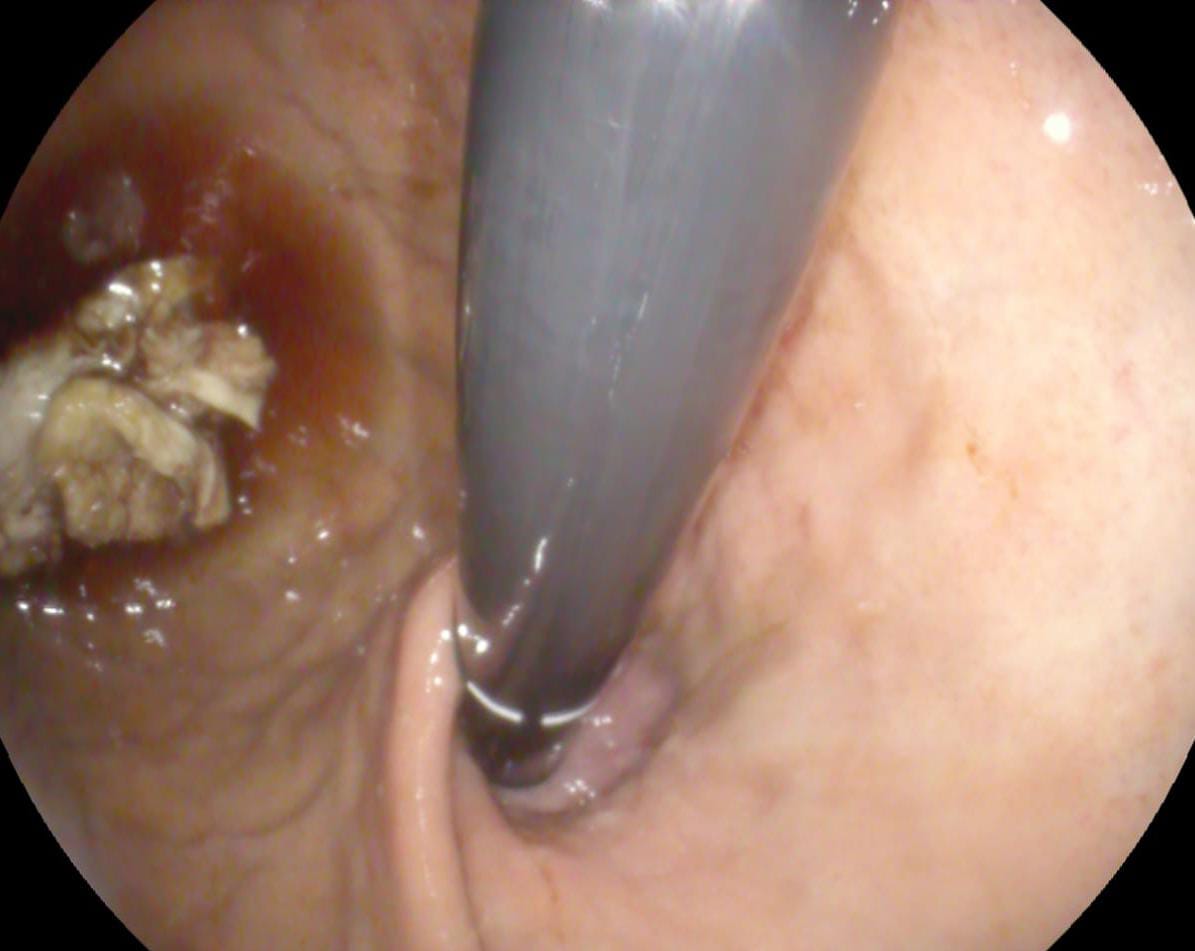

استقبل قسم مناظير الكبد والجهاز الهضمي بمستشفى أبو كبير المركزي طفل يبلغ من العمر 5 سنوات، يعاني من صعوبة في البلع والتنفس؛ نتيجة ابتلاع عملة معدنية أدت إلى انسداد مجرى الطعام.

على الفور تم التحضير لمنظار علوي طوارئ، وقام الفريق الطبي بقسم المناظير بمشاركة الدكتور عبدالمنعم زناتي، والدكتور صهيب إبراهيم، والدكتور عبدالستار محمد، والدكتور أسماء رزق، بالإضافة للدكتورة أسماء السيد استشاري التخدير، باستخراج العملة المعدنية من مرئ الطفل، وتم خروج الحالة من المستشفى بصحة جيدة.